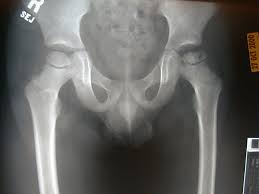

La enfermedad de Perthes es una enfermedad de la cadera del niño en la que se produce una debilidad progresiva de la cabeza del fémur y que puede provocar una deformidad permanente de la misma evitando la buena coherencia con el acetábulo (zona de la cadera donde debe entrar la cabeza del fémur para una correcta articulación)

Ocurre en niños entre los 3 y los 12 años y aparece con mayor frecuencia en niños (80%) que en niñas (20%). En la mayoría de los casos afecta sólo una cadera pero en el 10% de los pacientes la lesión se produce en ambos lados, aunque en estos casos no suele hacerlo nunca de forma simultánea.

La radiología depende del estadio evolutivo de la enfermedad, siendo las imágenes más características la deformidad y fragmentación de la cabeza femoral, con alternancia de zonas más transparentes con zonas opacas.